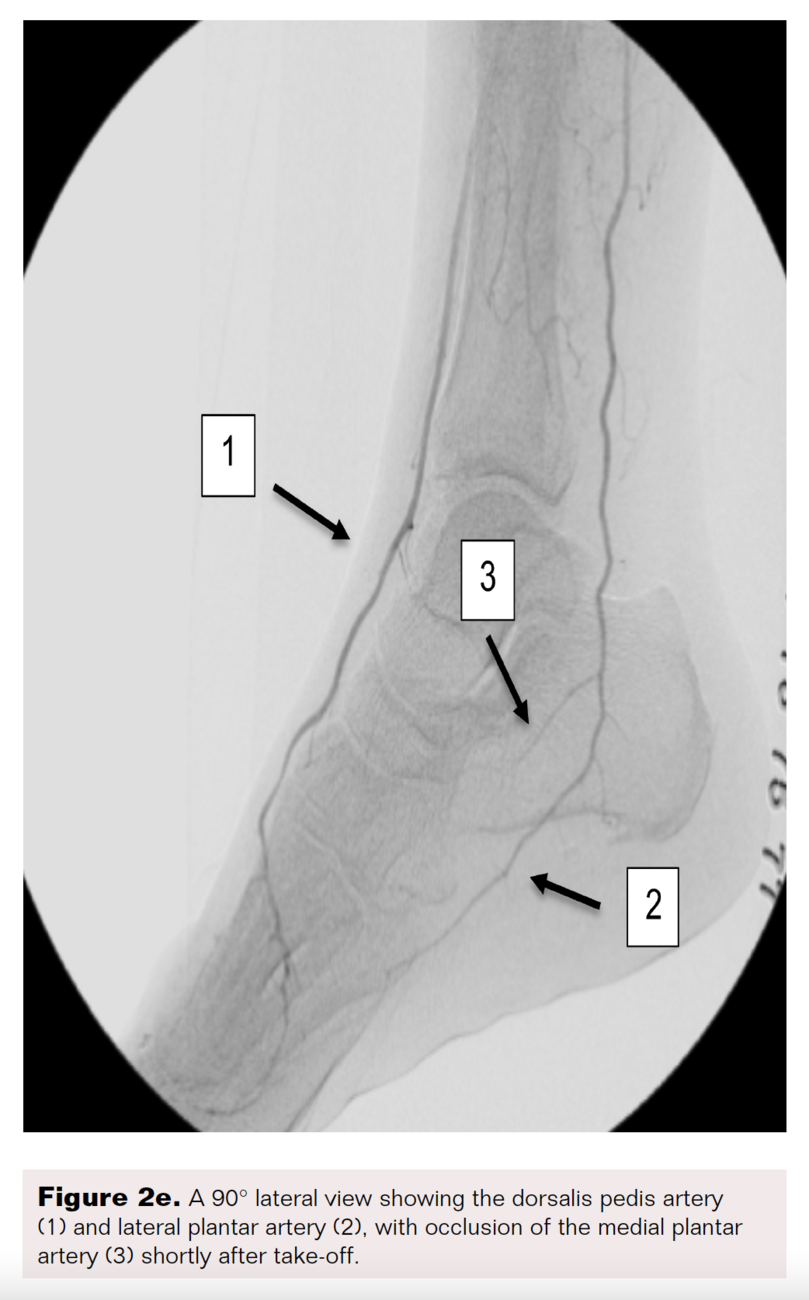

A right lower-extremity angiogram was performed using ultrasound guidance for antegrade access of the proximal superficial femoral artery (Figure 2A). Fluoroscopic acquisition demonstrated no significant disease in the superficial femoral artery (Figure 2B) and popliteal artery (Figure 2C), with no significant stenosis seen in the anterior tibial artery, PTA, and peroneal artery (Figure 2D). Pedal angiography demonstrated a complete pedal-plantar loop formed by the DPA and the lateral plantar artery (LPA) (Figure 2F).

However, the entirety of the medial plantar artery (MPA) distribution was chronically occluded shortly after take-off (Figure 2E and Figure 2F). Super-selective angiography revealed chronic total occlusion of the medial branch of the first common plantar digital artery arising from the first plantar metatarsal artery (Figure 2G). Angiography also revealed an occluded accessory branch arising medially from the superficial branch of the MPA.